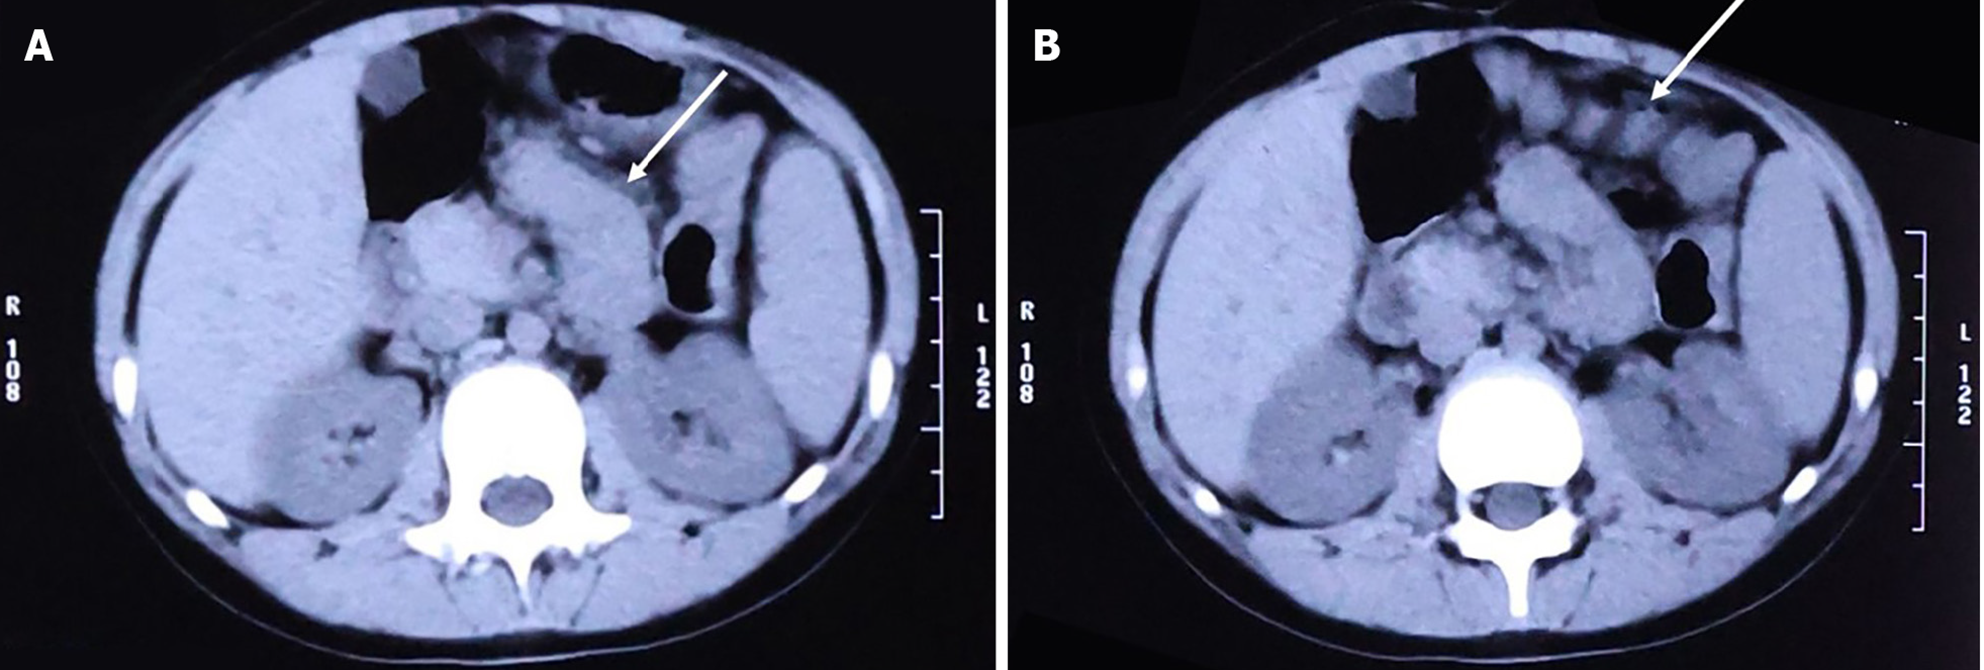

Because emergency examinations suggested signs of acute intestinal obstruction, the child was transferred to the Pediatric Surgery Department for further treatment. We proceeded with an abdominal computed tomography (CT) scan, the results of which were consistent with changes indicative of intestinal obstruction: (1) The intestinal tract within the abdominal cavity was disorganized, with a significant number of air-fluid levels visible (Figure 2A); (2) The obstruction point was located below and to the left of the umbilicus; the proximal small intestine was situated in the pelvic cavity and contained a large amount of intestinal content (Figure 2B); (3) The intestinal wall at the point of obstruction was markedly thickened, with pronounced exudation from the surrounding intestinal tract (Figure 2C); (4) The colon and rectum were collapsed (Figure 2D); and (5) Soft tissue structures were observed surrounding the small intestine, enveloping it and exhibiting a distinctive "accordion-like" appearance (Figure 3A and B).

Although imaging manifestations lack specificity, some useful clues can still be identified, especially on CT scans. “Cauliflower-like” arrangement, “bottle-gourd” appearance, and “concertina-like” arrangement can be found on the imaging scans of SEP patients[22,23]. In recent reports, one or more of these features can be identified on CT or magnetic resonance imaging scans[13,16,24,25]. These features were also observed in our case (Figure 3A and B).